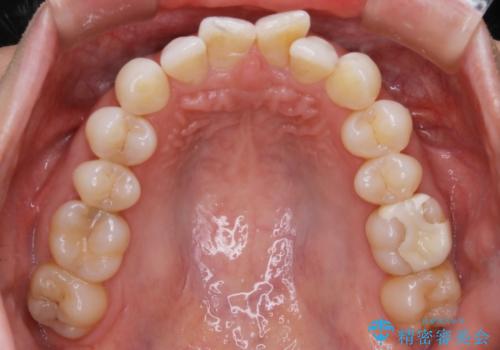

【抜歯】矯正治療とインプラントで正常な噛み合わせを実現

- 元々は矯正治療を主訴にご来院されました。

治療を始めるにあたり、精密検査を受けていただき全体の状況を把握したうえで矯正治療の計画を立てることとなりました。

その過程で左下の6番目の歯は治療が必要な状態であることが分かり、被せ物を外して内部を確認してみると根が破折してしまっていることが判明しました。

歯が深い位置で破折している場合は基本的には抜歯が選択されます。

様々な治療プランを患者さんと相談させて頂き、最終的にインプラントで噛み合わせを回復させていくこととなり、まず悪くなっている歯を抜歯することから開始しました。